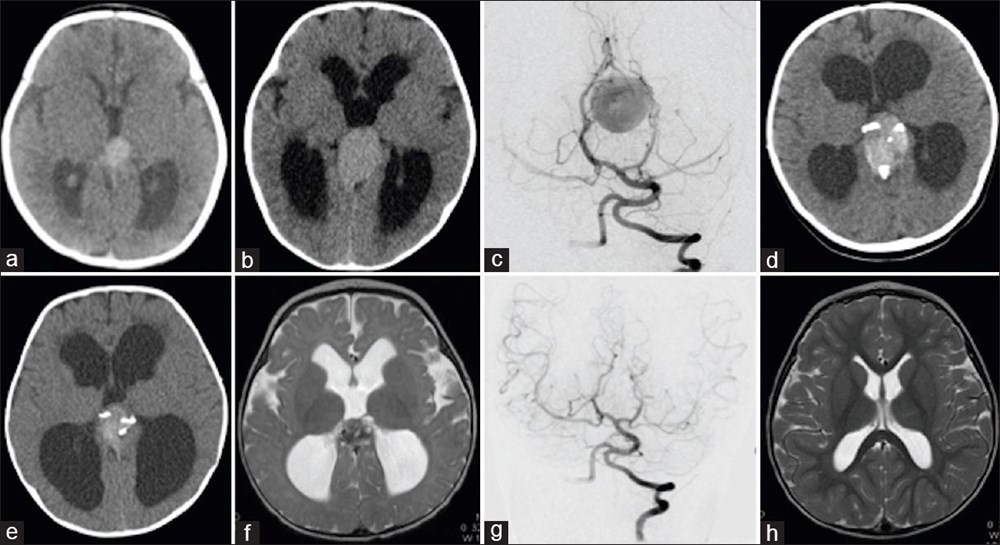

Bununla birlikte, Galen Damar Malformasyonu (VOGM) her yıl yüzlerce bebeği etkiliyor ve çocuklar doğumun ilk birkaç gününden sonra hayatta kalamayabiliyor. Hastalık, beyindeki atardamarların kanı kılcal damarlar yerine doğrudan toplardamarlara akıtmasına neden olarak kalbin boğulmasına ve beyin hasarına yol açıyor.

Mevcut tedaviler ise şimdiye kadar bebeğin doğumundan sonrası ile sınırlıydı, ancak bu noktada çoğu vakada beyin hasarı çoktan meydana gelmiş oluyordu.

“Stroke” adlı bilimsel dergide sonuçları açıklanan yeni cerrahi operasyon, hastalığı bebeği etkilemeden önce iyileştirmeyi amaçlıyor.

Dr. Orbach, “Bu yaklaşım, Galen Damarı Malformasyonu’nun tedavisinde büyük bir potansiyele sahip. Malformasyonu doğumdan önce onarıyoruz ve doğumdan sonra tersine çevirmeye çalışmak yerine kalp yetmezliğini ortaya çıkmadan önlüyoruz. Bu, bu bebekler arasında uzun vadeli beyin hasarı, sakatlık veya ölüm riskini önemli ölçüde azaltabilir.” diye konuştu.